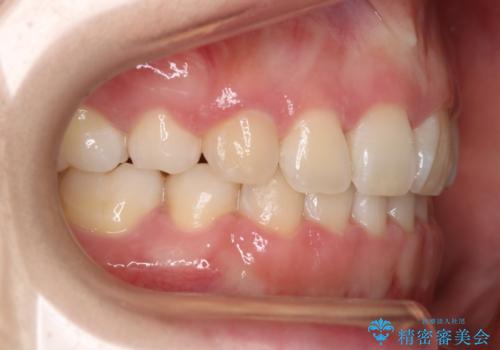

- 前歯のガタつきと口元の改善を主訴に来院されました。

結果的に表の装置よりは期間が掛かりましたが、口元もしっかり下がり韓国美人な横顔になったと患者様にも喜んでいただけました。